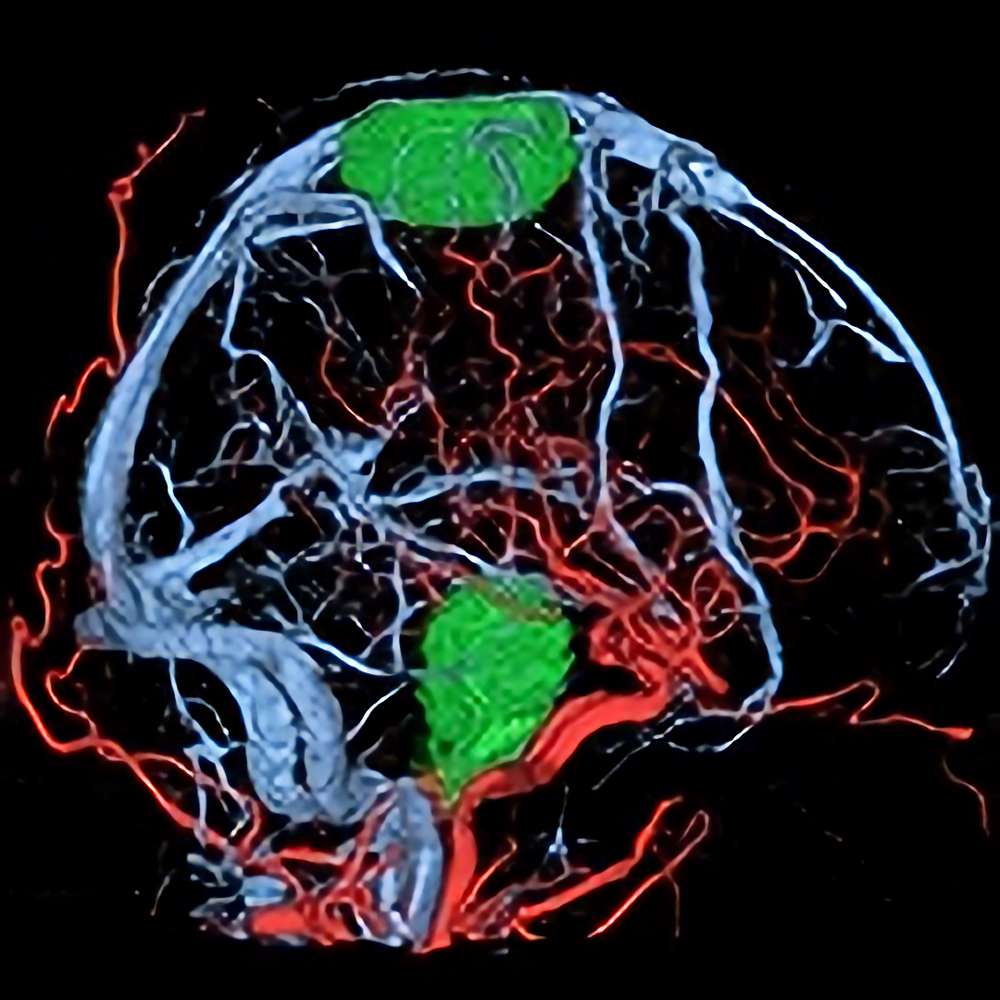

脳動静脈奇形

血管塞栓術

松田/濵田/元永